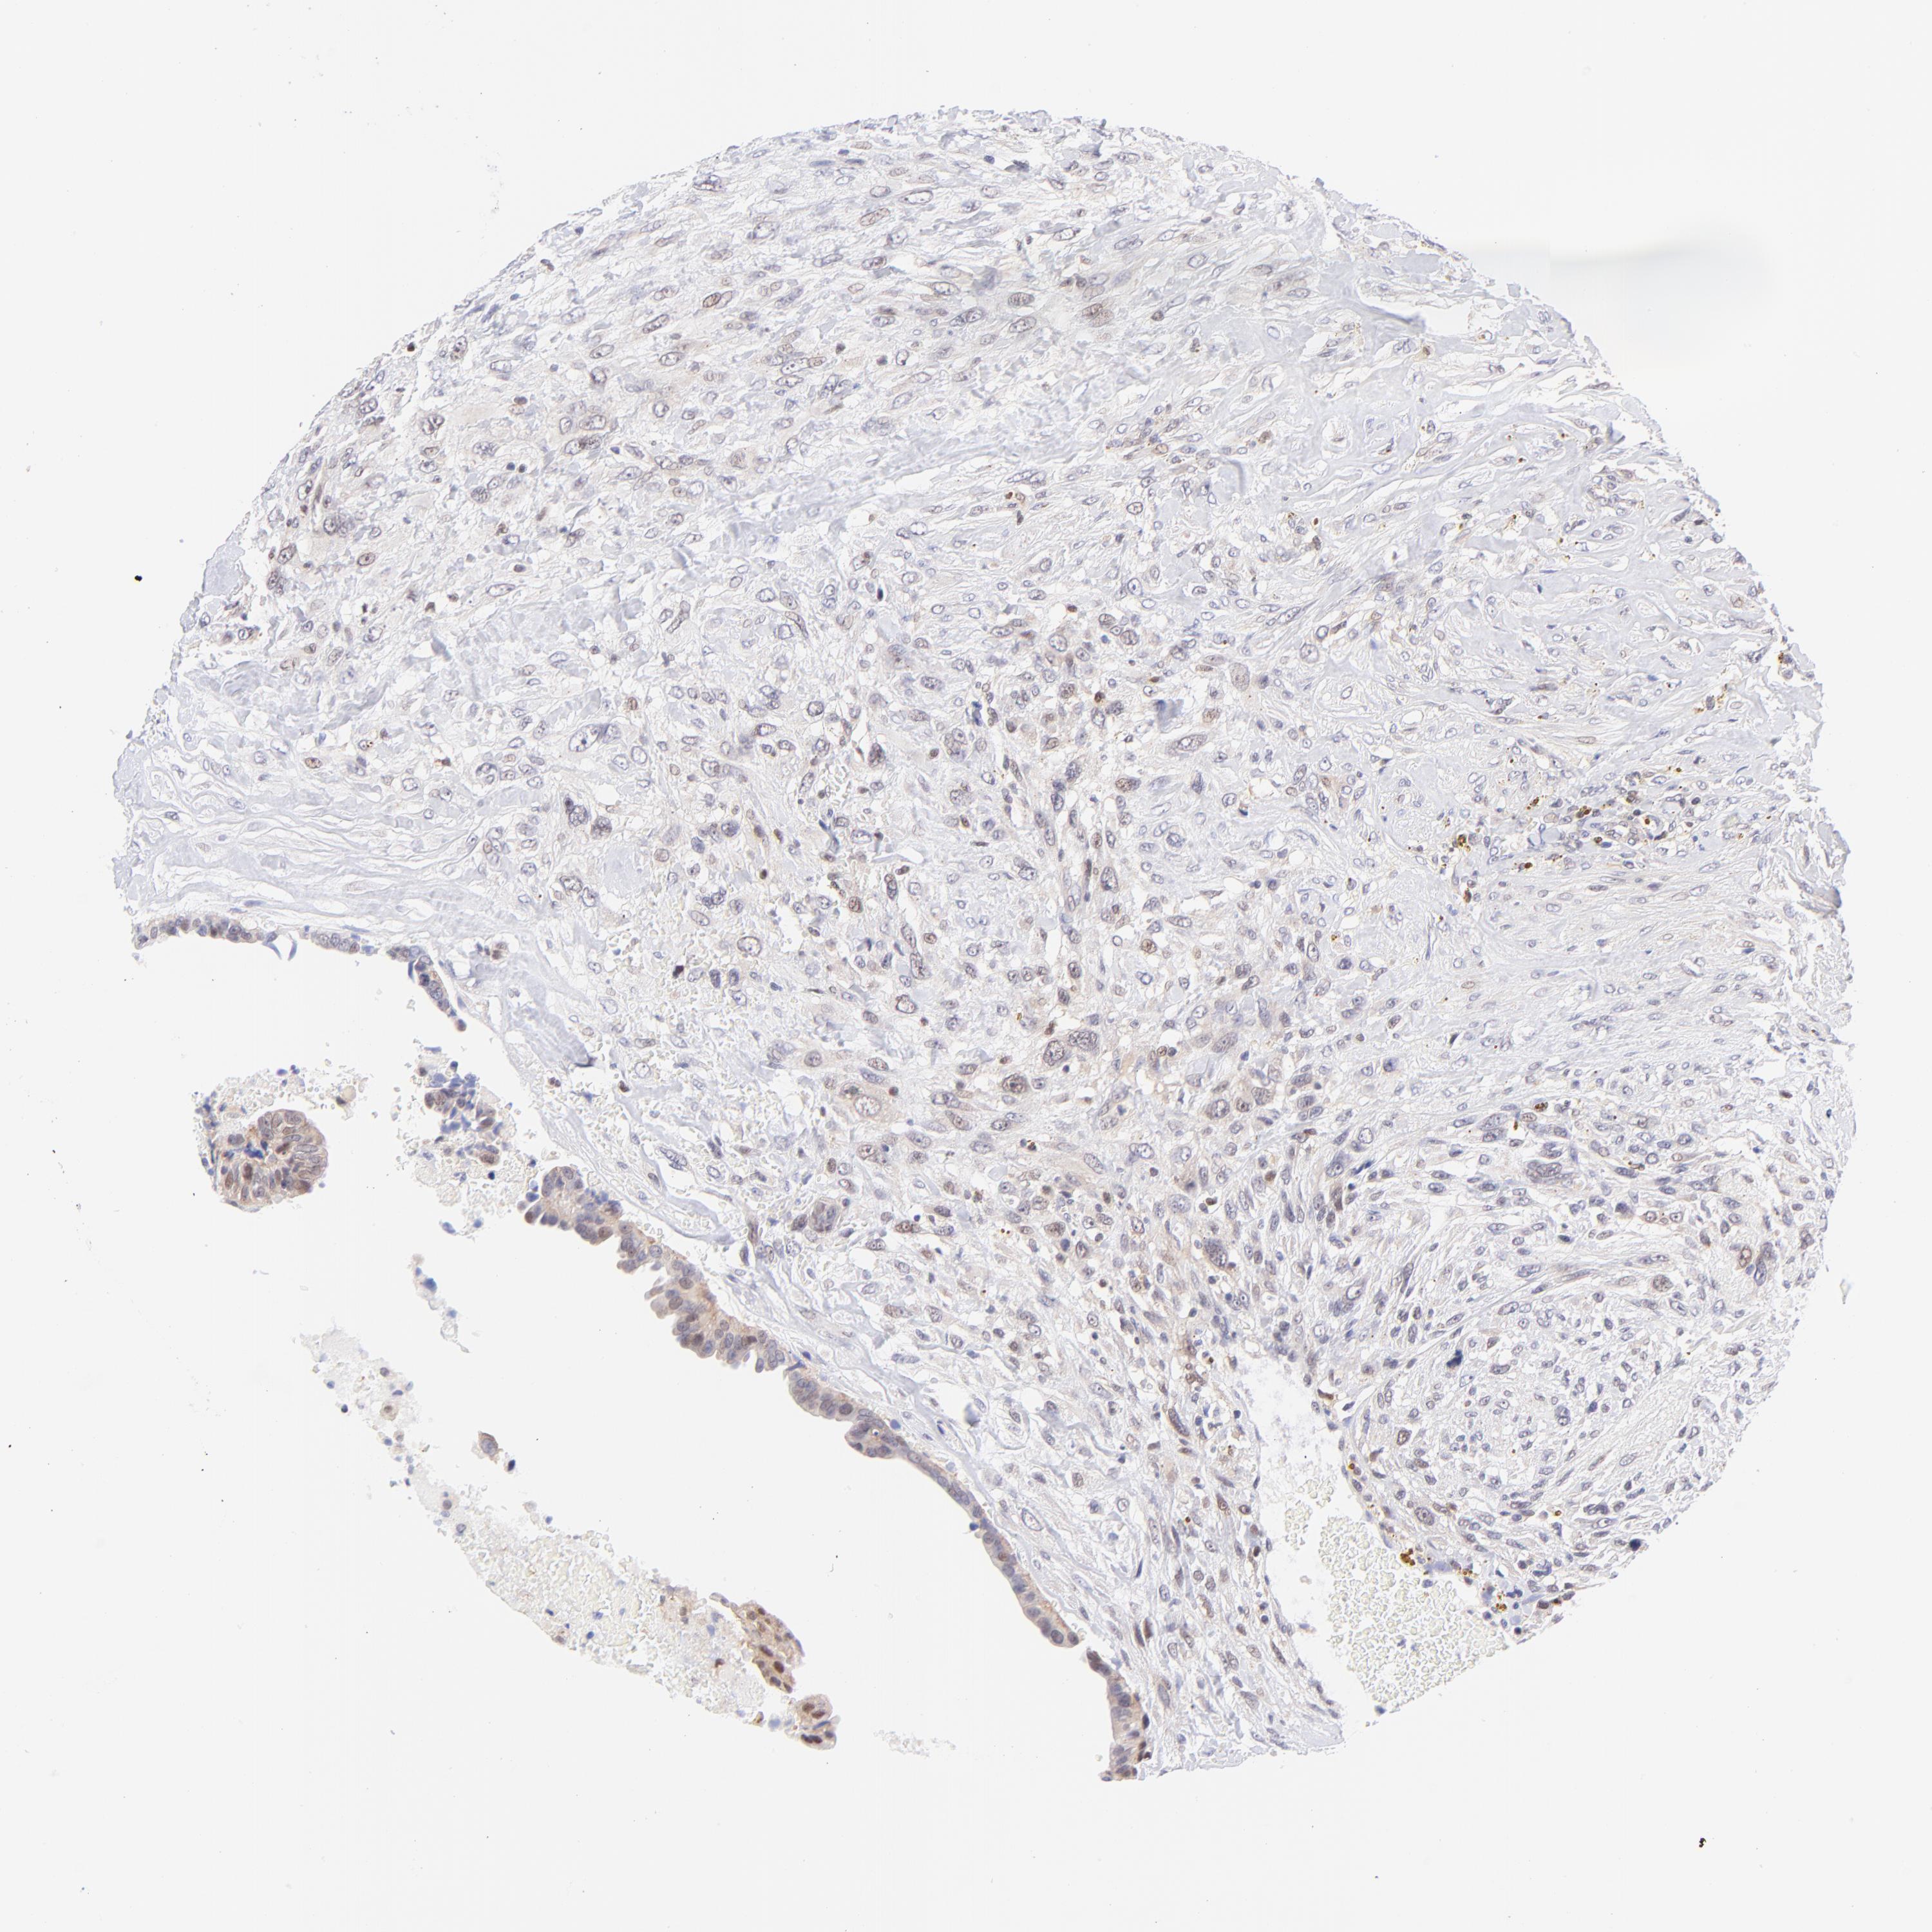

CANCER BREAST CANCER Show tissue menu

BRCA TCGA BRCA VALIDATION PROTEIN EXPRESSION

Breast cancer

Human cancer

Breast invasive carcinoma